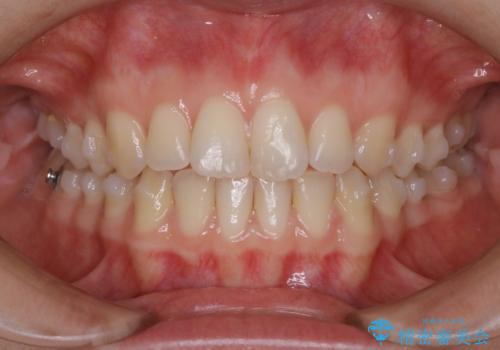

- 上下前歯のがたつきが気になるとご相談にいらした方です。

一見前歯のがたつきだけ改善させれば良い様に見えますが、このがたつきの原因は奥歯の嚙み合わせのズレからくるものであったため、インビザラインFULLで噛み合わせの改善から行っていきました。前歯の角度も改善されたために頑張って唇を閉じる必要がなくなり、横顔のシルエットも綺麗になりました。

前歯のがたつきだけを治そうとした場合、噛み合わせは二の次なってしまう事が多く、せっかく綺麗になった歯並びも後戻りしやすくなります。奥歯の噛み合わせからしっかり機能させることで、長期間にわたって綺麗な歯並びを保ちやすくなります。

インビザライン20時間以上正しく装着していただいたおかげもあり、短期間で治療することが出来ました。